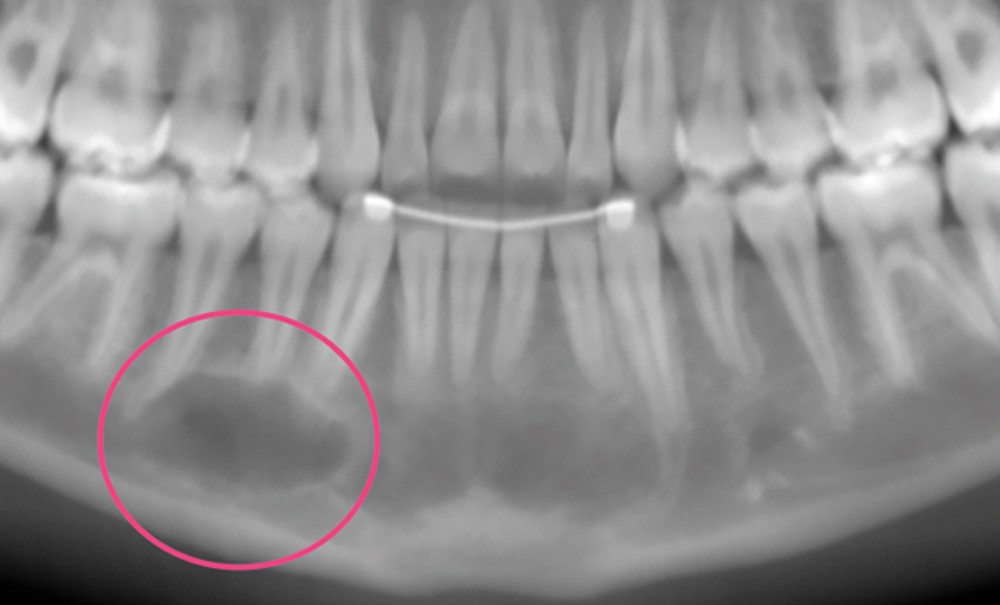

Le kyste osseux solitaire, aussi appelé kyste osseux essentiel (KOE) ou kyste osseux simple, est un pseudo-kyste dépourvu de paroi épithéliale. Il s’agit d’une lésion intra-osseuse vide de contenu ou remplie d’un liquide séreux ou séro-hématique. Au niveau de la sphère faciale, sa localisation privilégiée est la symphyse et le corps de la mandibule (fig. 1). Il touche plus exceptionnellement le maxillaire. Son pic d’incidence se situe à la 2e décennie avec un sexe ratio de 1 lorsqu’il est isolé. Lorsqu’il est associé à une dysplasie cémento-osseuse floride, le KOE touche préférentiellement les femmes d’âge adulte mélanodermes.  Bien que plusieurs hypothèses étiopathogéniques aient été proposées – incluant le traumatisme, la dégénérescence tumorale, l’ischémie osseuse, et les anomalies du remodelage osseux –, l’étiologie exacte de cette lésion reste indéterminée.